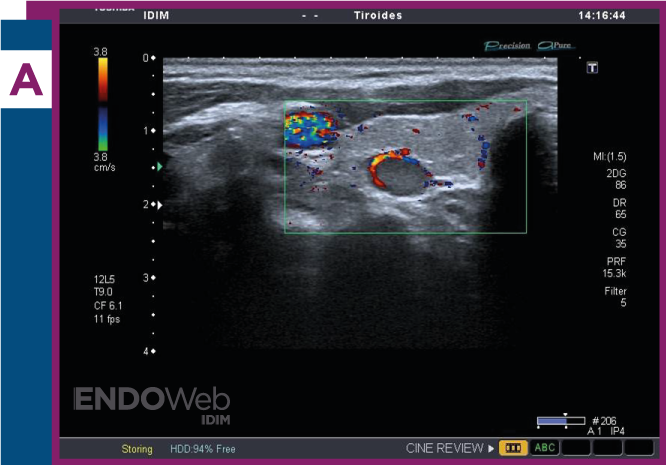

Paciente mujer de 55 años, con diagnóstico de hiperparatidoidismo primario, a quien se le solicita ecografía de cuello, para búsqueda de lesión paratiroidea

Laboratorio: Calcemia 11.2mg/dL, fosfatemia 1.9mg/dL, PTHintacta 128 pg/mL, 25OHvitamina D 33 ng/mL

Ecografía cervical, donde se observa en topografía paratiroidea, nódulo sólido e hipoecoico, con imagen al doppler compatible con signo del arco vascular que rodea nódulo paratiroideo en más de 180° de su contorno y se visualiza en las imágenes al doppler color (A) y doppler power (B).